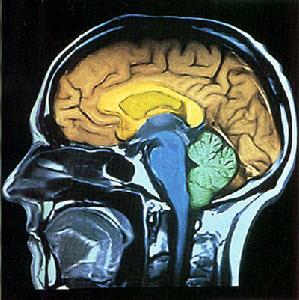

3頭顱CT掃描

4磁共振(MRI)